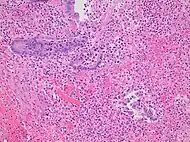

Pathology diagnosis of appendicitis can be made by detecting a neutrophilic infiltrate of the muscularis propria.

Micrograph of appendicitis and periappendicitis. H&E stain

Micrograph of appendicitis showing neutrophils in the muscularis propria. H&E stain

Acute suppurative appendicitis with perforation (at right). H&E stain

| Pattern | Gross pathology | Light microscopy | Image | Clinical significance |

|---|---|---|---|---|

| Acute intraluminal inflammation | None visible |

|

![]() |

Probably none |

| Acuta mucosal inflammation | None visible |

May be secondary to enteritis. | |

| Suppurative acute appendicitis | May be inapparent.

Can be presumed to be the primary cause of symptoms |

| Gangrenous/necrotizing appendicitis |

Will perforate if untreated |

| Periappendicitis | May be inapparent.

If isolated, probably secondary to other disease |